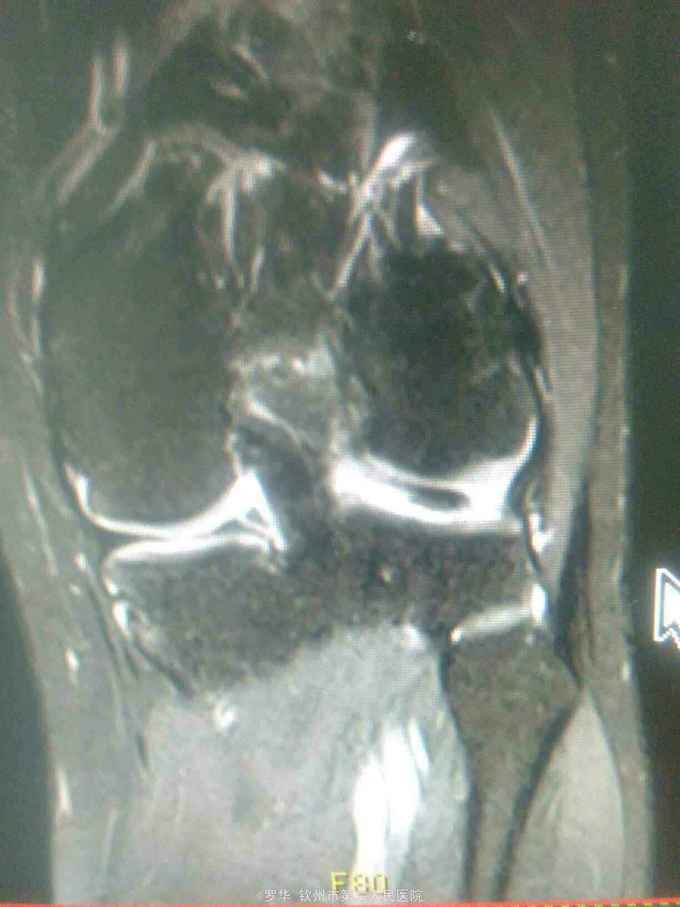

主诉:扭伤致左膝关节活动受限3月余。病史:患者男性,31岁,于入院3月余前扭伤左膝关节,致左膝关节肿痛、活动受限,尚可站立行走,但不能剧烈运动及重体力劳动,曾行磁共振检查提示左膝前交叉韧带损伤,半月板损伤,现为进上一步治疗入院。

查体:左膝关节无明显压痛,前抽屉试验阳性,侧方应力试验、麦氏征、研磨试验均阴性,膝关节屈伸活动可,余查体未见特殊。 辅查:膝关节磁共振提示左前交叉韧带损伤,左膝关节半月板损伤。

诊断:左膝关节前交叉韧带断裂,左膝关节半月板损伤。 治疗:予硬外麻下行左膝关节前交叉韧带重建术。